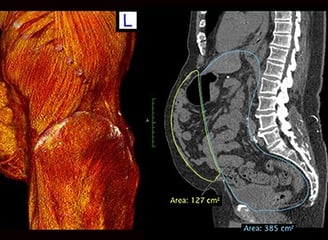

To optimize outcomes, Dr. Hernández employs preconditioning techniques before surgery, including Botulinum toxin type A (BTX) injections and progressive pneumoperitoneum (PPP), which enhance the flexibility and compliance of the abdominal wall.